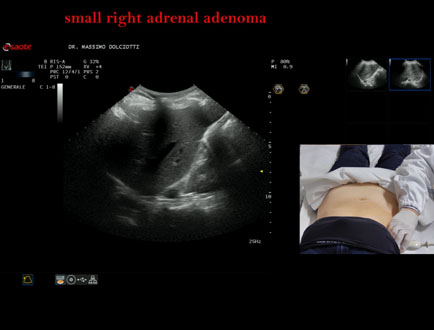

Età Paziente: F 69 anni

Motivazione dell'esame: follow up per piccolo adenoma surrenalico.

Commento all'esame: le immagini ed il video documentano in sede surrenalica destra, formazione ipoecogena, a margini definiti, rotondeggiante, delle dimensioni di 15,8 x 14,8 mm, da ricondurre ad adenoma surrenalico.

Conclusioni: piccolo adenoma surrenalico destro (small right adrenal adenoma).

Presentazione: Dr. Massimo Dolciotti - Ancona

Elaborazione digitale: Andrea Dini - Ancona